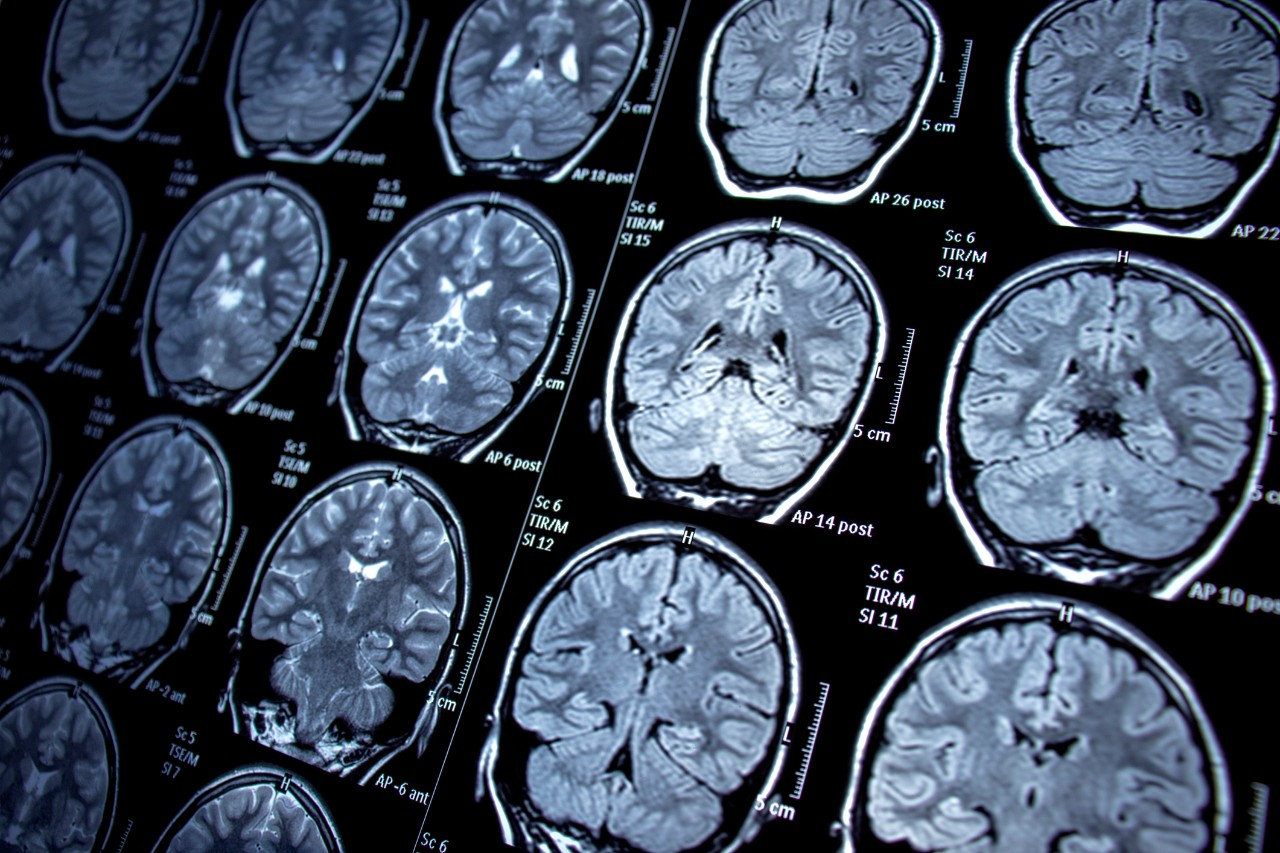

Researchers at the University of Cincinnati and Dell Medical School at the University of Texas at Austin (Dell Med) are leading a study using state-of-the-art neuroimaging techniques and artificial intelligence to identify changes in the brains among children of adults living with bipolar disorder — a debilitating condition that interferes with daily life due to its dramatic mood, energy and activity level shifts.

The study is the first of its kind to focus specifically on the progression of the disease over time via neuroimaging in children of parents with bipolar disorder.

The research leverages AI algorithms to discern variations in participants’ brains, combining imaging data with cognitive, clinical, early life adversity and psychosocial function measures. The result is a precise delineation of brain maturation for each person at risk of developing bipolar disorder.

The five-year longitudinal study uses functional magnetic resonance imaging to identify early signs that the brain is developing bipolar disorder. Participants ages 14-21 — a critical time when mania symptoms often develop — undergo annual brain scans to track changes in the brain. If they become depressed, suicidal or experience mania, the participants undergo additional brain scans to help researchers understand how the damage is unfolding.

Featured photo at top of brain scans. Photo/Nur Ceren Demir/iStock.